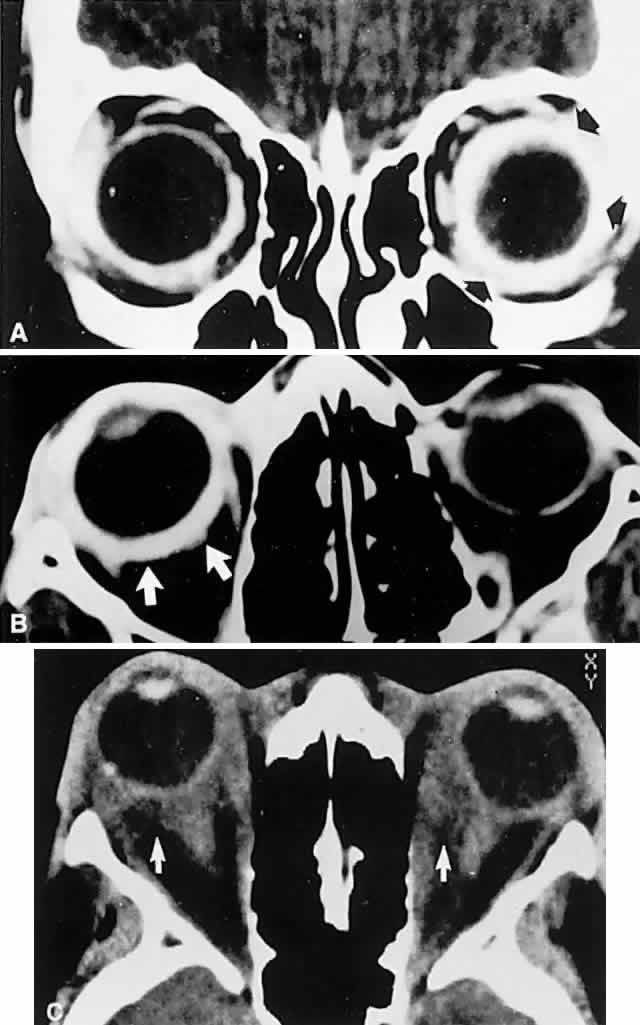

Orbital pseudotumor and the Tolosa-Hunt syndrome are likely the same process, varying only in that the idiopathic inflammation involves predominantly the orbit in the former and predominantly the superior orbital fissure and/or the anterior cavernous sinus in the latter. Idiopathic inflammation is a diagnosis of exclusion, made only in a fairly circumscribed clinical context, and when other pathologic processes have been ruled out. In this regard, contrast-enhanced CT scan or MRI shows diffuse infiltration or focal lesions, usually with notable enhancement of the posterior wall of the globe (Fig. 15). With proper orbital imaging and ultrasonographic assessment as diagnostic procedures, tissue biopsy is rarely necessary, and the response to systemic corticosteroid administration is usually dramatic, if not diagnostic (see also Volume 2, Chapter 12).

Fig. 15. Contrast-enhanced computed tomography (CT) scan in patient with painful ophthalmoplegia, lid swelling, and proptosis. In unilateral case, note enhancing envelope of thickened sclera (arrows) on coronal (A) and axial (B) sections of left globe. C. Bilateral orbital pseudotumor shows shaggy infiltration of orbital soft tissues (arrows) surrounding globes and optic nerves.